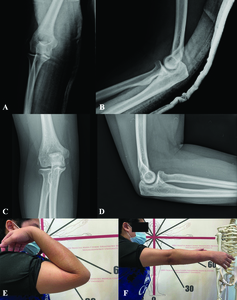

In this case, we performed arthroscopic Lateral Collateral Ligament Repair to restore the osteoligamentous structures and provide elbow stability. Perioperatively, examination of the patient’s elbow under anesthesia revealed a positive posterolateral drawer test and fluoroscopic varus stress test, further supporting our impression. The patient was then set in a lateral decubitus position with proximal arm support. The sterile drape was prepared from the fingertip up to the tourniquet area, initially applied at her proximal arm. Arthroscopic anterior compartment examination was done via the proximal anteromedial portal, and evidence of capsular tear and joint space widening was recorded (Fig. 2A).

Arthroscopic lavage was performed to remove the cartilaginous loose body. Then we continued with the posterior compartment for lateral collateral ligament repair. The posterior portal was used as a viewing portal, whereas the posterolateral portal worked. As a result, ulnohumeral distance widening and drive-through sign were observed (Fig. 2B). Moreover, a bony avulsion of the LCL from the lateral epicondyle was visualized (Fig. 2C).

Next, the LCL humeral footprint and stump were debrided, preparing them for the application of suture anchor. A soft anchor (1.8-mm double-loaded Y-Knot® Flex, ConMed) was inserted at the lateral epicondyle. A small skin incision was made posterior to the radial head and dissected to expose the anconeus fascia. Following annular ligament identification, the suture passer was pierced through the previous incision, first through the anconeus fascia and then the annular ligament (Fig. 2D). One end of the suture anchor was retrieved back to the incision through this tract. The steps mentioned were repeated for another suture strand (Fig. 2E).

A subcutaneous tunnel was created from the previous incision toward the posterolateral portal. The sutures’ ends from the posterolateral portal were retrieved from the incision through this tunnel. Lastly, sutures were tied over the anconeus fascia to repair and imbricate the LCL (Fig.2F). After the repair, the drive-through sign and ulnohumeral opening gap were confirmed negative. Likewise, elbow stability was examined, and no subluxation resulted during end extension. The patient was immobilized with a long arm splint, and the elbow joint was congruent after the operation (Fig.3A-B).